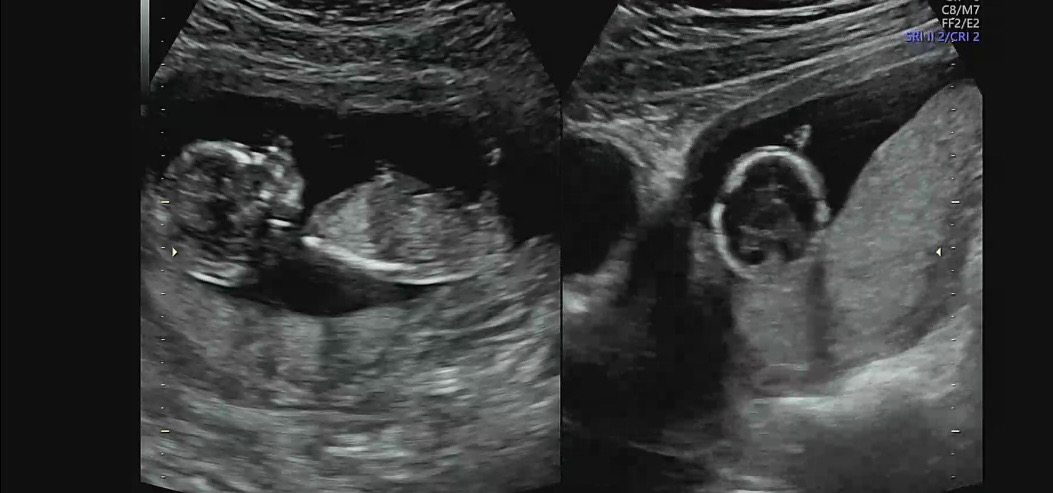

각도법좀 봐주세요!!

12주차에 독감에 걸려버려서 겨우겨우 13주 되자말자 기형아검사 통과했는데 성별이 너무너무 궁금해요ㅠㅠ 고수님들 부탁두려요!!